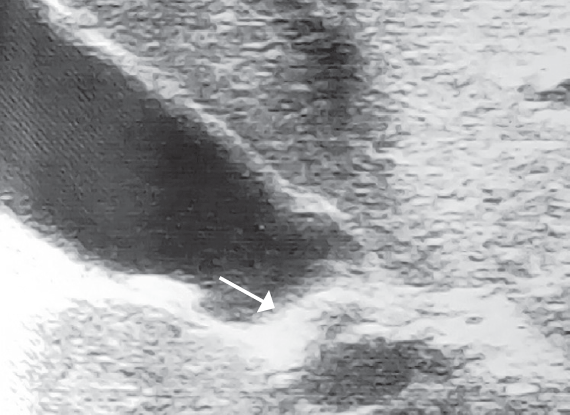

После установления диагноза ЖКБ всем пациентам проводилась обзорная рентгенография брюшной полости с целью обнаружения кальцинированных конкрементов в желчном пузыре. У двух пациентов они были четко визуализированы, вследствие чего детям консервативное лечение не проводилось и были установлены показания к оперативному лечению (рис. 3).

Рис. 3. Кальцинированный конкремент в желчном пузыре

Fig. 3. Calcified brupor in the gallbladder